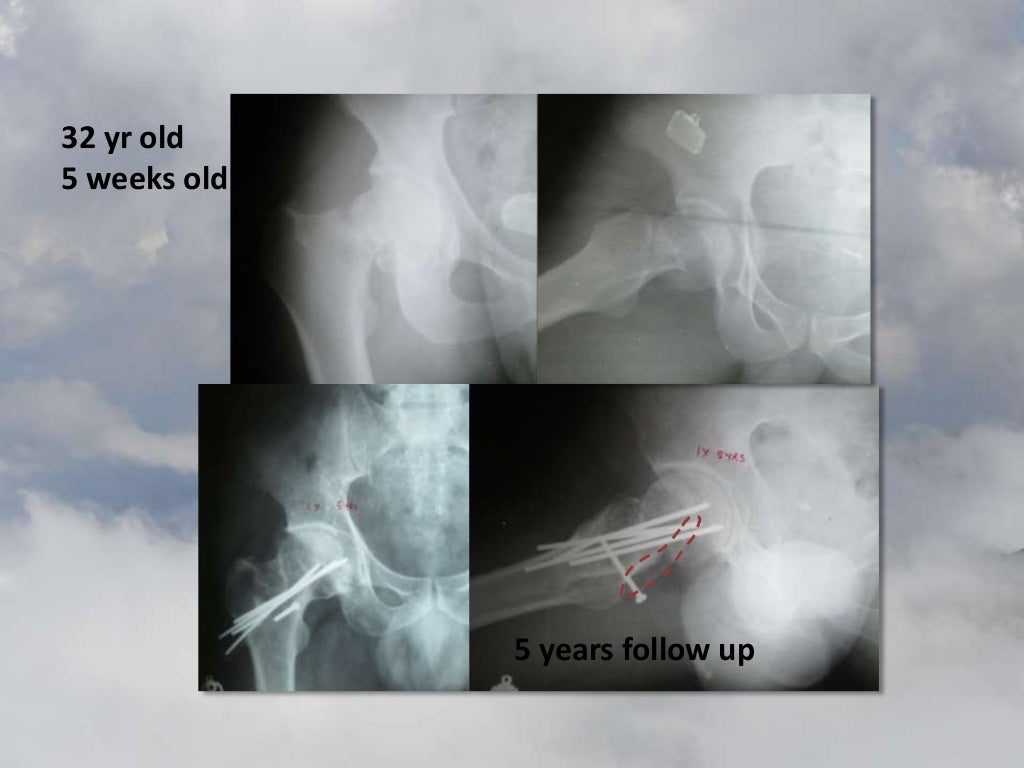

Muscle pedicle grafting for preservation of the Hip by Prof. V.S.Ravi… Grafting Muscles The term graft is commonly used to refer to either an allograft or an autograft. As a standalone procedure, facial fat grafting saw a 1% rise in the us in 2023 for a total of about 34,000 procedures (a far cry from the 5.3 million hyaluronic acid filler procedures performed. Muscle implants and muscle fat grafting are two procedures available. Grafting Muscles.

Muscle pedicle grafting for preservation of the Hip by Prof. V.S.Ravi… Grafting Muscles The term graft is commonly used to refer to either an allograft or an autograft. In this article, we propose several modern modifications and perioperative interventions that improve outcomes in our practices. Learn about the fascinating process of muscle grafting, a surgical procedure that transfers healthy muscle tissue to repair and improve. As a standalone procedure, facial fat grafting saw. Grafting Muscles.